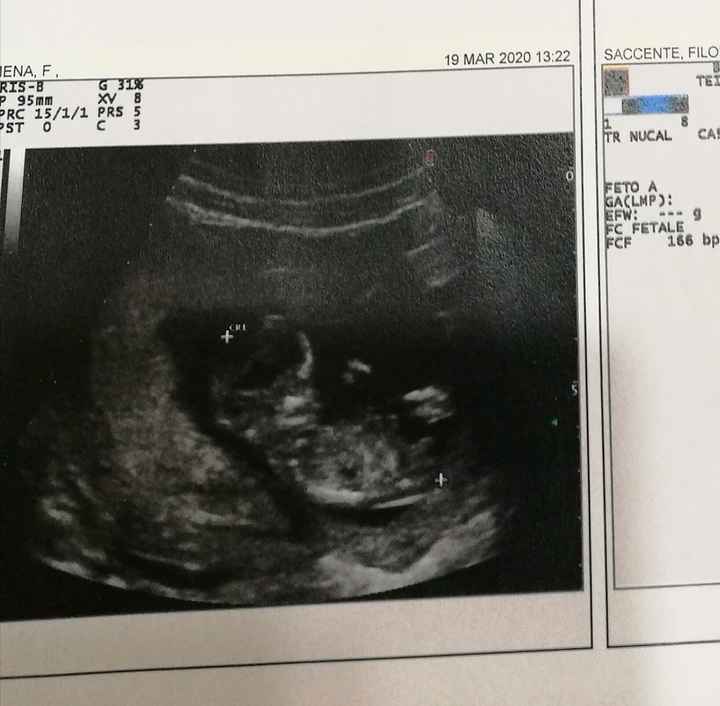

Ecografia,. Maschio o femmina? 5

Buonasera ragazze sono nuova in questo gruppo volevo chiedere a voi se mi sapreste dire se è un maschietto o una femminuccia

Buonasera a tutte ragazze sono nuova in questo gruppo volevo chiedere a qualcuna di voi se mi potete aiutare a capire se il mio bimbo è un maschietto o una femminuccia